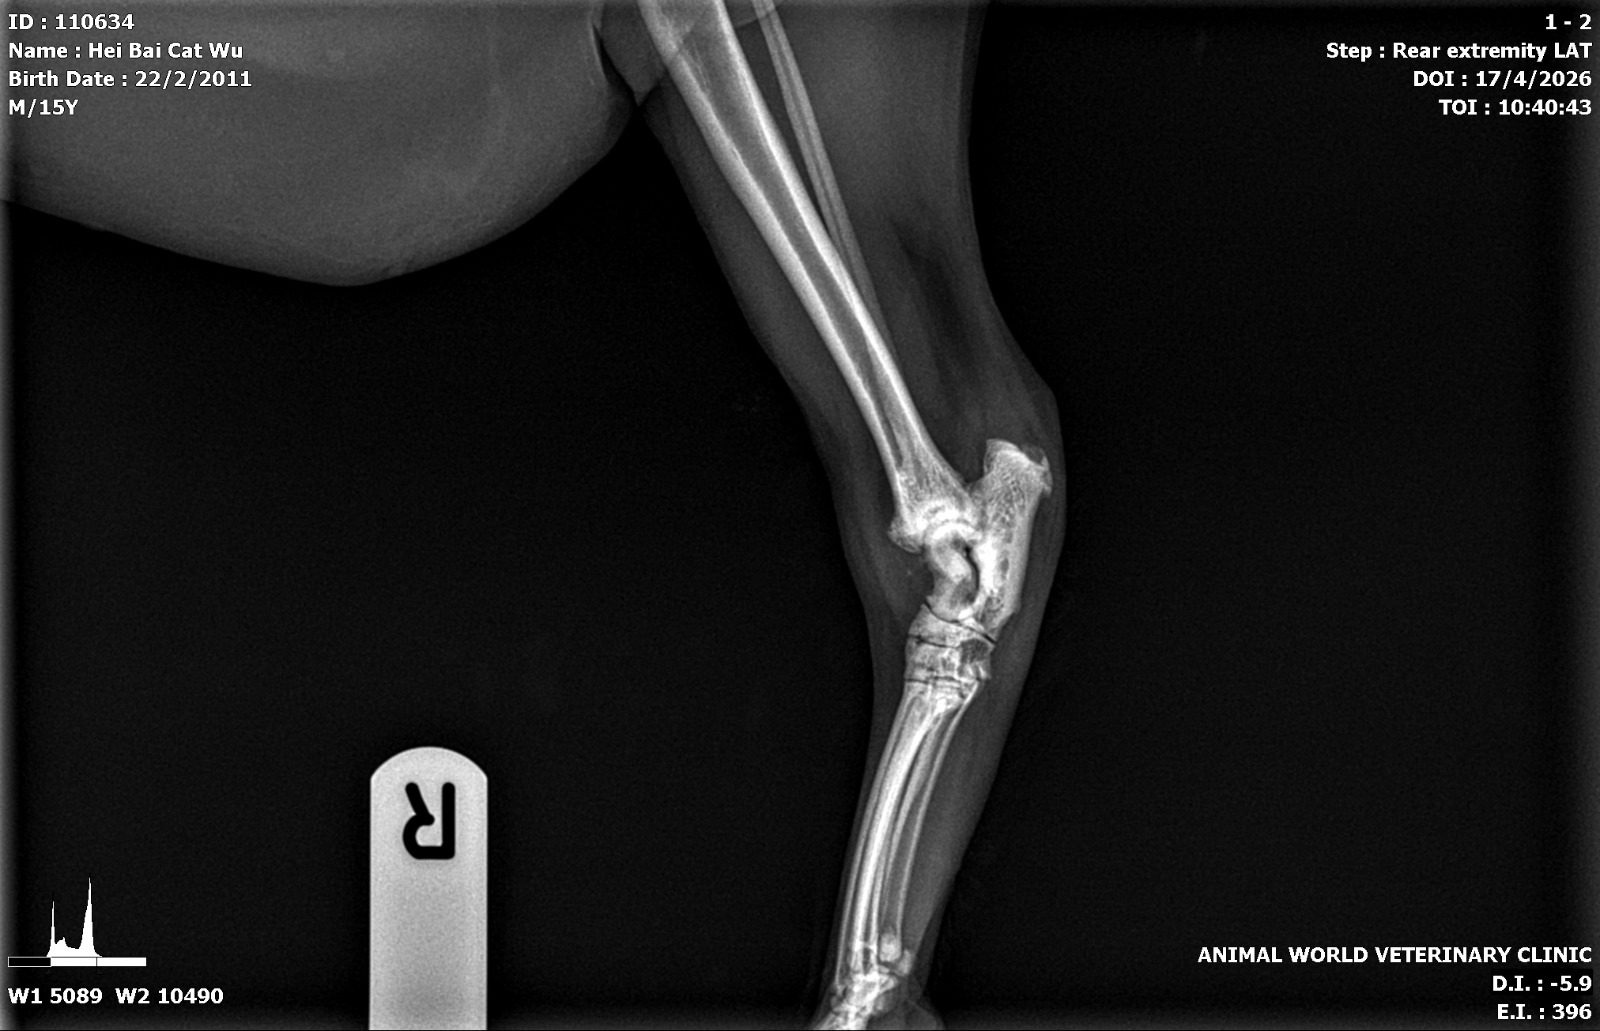

“Left hock

Green arrows – lots of osteophytes/arthritis

Red arrow – suspected fractured site but ideally need VD view

General bone density of hock bone more porous than usual”

“Right hock

Green arrows – osteophyte

Blue arrow – this lysis area in both legs”